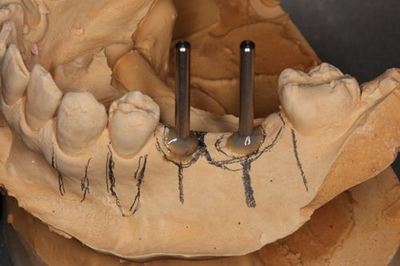

KaVo プロターevo7 咬合器にマウントしました。

スターティングポイントのマーキングのために準備をします。

近心側は角度も決めていますが、

遠心側はスターティングポイントのマークまでの役割です。

便宜的に平行にしてサージカルステントが着脱できるようにしています。